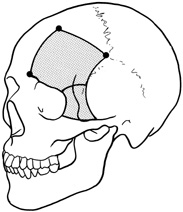

The transcranial orbitotomy uses a frontal craniotomy with removal of a portion of the orbital roof to expose the orbital apex or superior orbit. This is best performed by a neurosurgeon familiar with skull-base surgical approaches. In most cases, the supraorbital rim over the involved side is removed en bloc with the frontal bone flap (Fig. 13). The anterior one-half or two-thirds of the orbital roof breaks free with removal of the rim and frontal bone flap, and the remaining posterior portion of the roof can be removed with rongeurs. Historically, it was suggested that all orbital tumors be removed via craniotomy, because before the imaging era it was difficult to anticipate the intraorbital location of a mass.18 The transfrontal approach was first described by Jones10 in 1970. Jane and colleagues19 proposed the current technique in 1982. Refinements have been discussed by Maroon and Kennerdell9 and Housepian.20 This operation has been termed the panoramic orbitotomy by Rootman21 because of the wide area of exposure offered by this procedure.

Fig. 13. Schematic diagram for transcranial orbitotomy in which the supraorbital rim is removed en bloc with the frontal bone flap. This provides extensive exposure to the superior and lateral orbit.